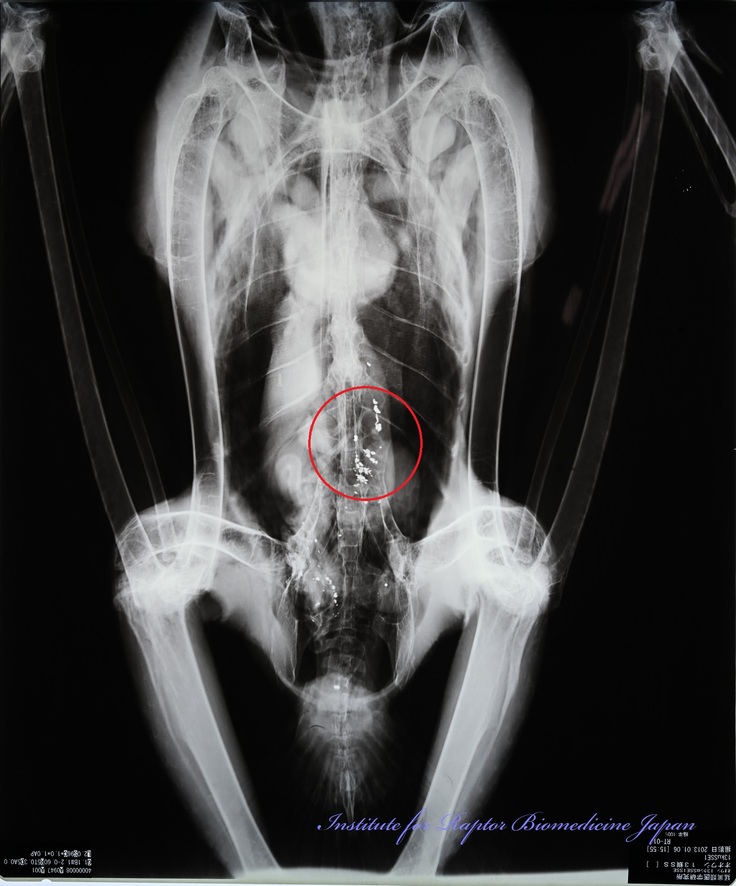

エゾシカ猟が始まっているが、まだオオワシやオジロワシの鉛中毒は発生していない。狩猟の際に鉛弾が使われ、獲物の肉や内臓が放置されたり、半矢になった獲物が別の場所で死ぬと、採食した猛禽類が肉中の鉛弾を飲み込み鉛中毒になる。今年こそ鉛中毒発生0年になって欲しい!

写真:赤丸はオオワシの胃内で確認された鉛ライフル弾の破片